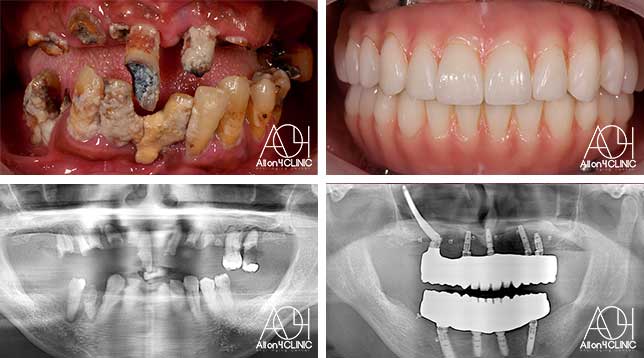

女性 / 42歳

歯がボロボロなのは分かっているが、時間的な余裕が無いことと歯科に対する恐怖心から、悪いままの状態を放置してしまった。人前でおもいっきり笑いたいので意を決して来院。

治療詳細: ガイデッドサージェリーにてインプラント埋入。歯槽骨が残っていたため歯冠形態のみ(ガム無し)の補綴

費用:¥3,850,000(税込) 『モニター割引適用』

リスク:治療後の口腔管理が不適切な場合、埋入したインプラント周囲に感染・炎症を起こし、脱落する可能性がございます。